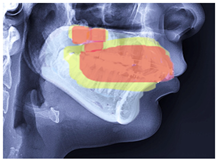

2.2. ROI Handcrafted Feature Detection

2.3. ROI Identification, YOLO-UNet-Based